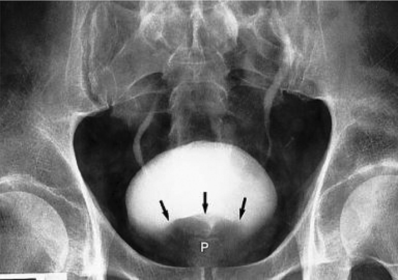

Prostatic Hypertrophy Prostate gland enlargement along with urinary output obstruction Common in males over 55 years of age Symptoms: reduced urine output along with sensation of full bladder Radiographic Appearance: borders of the bladder appear lumpy and irregular, base of the bladder has a notched appearance due to the enlarged prostate pushing up against it